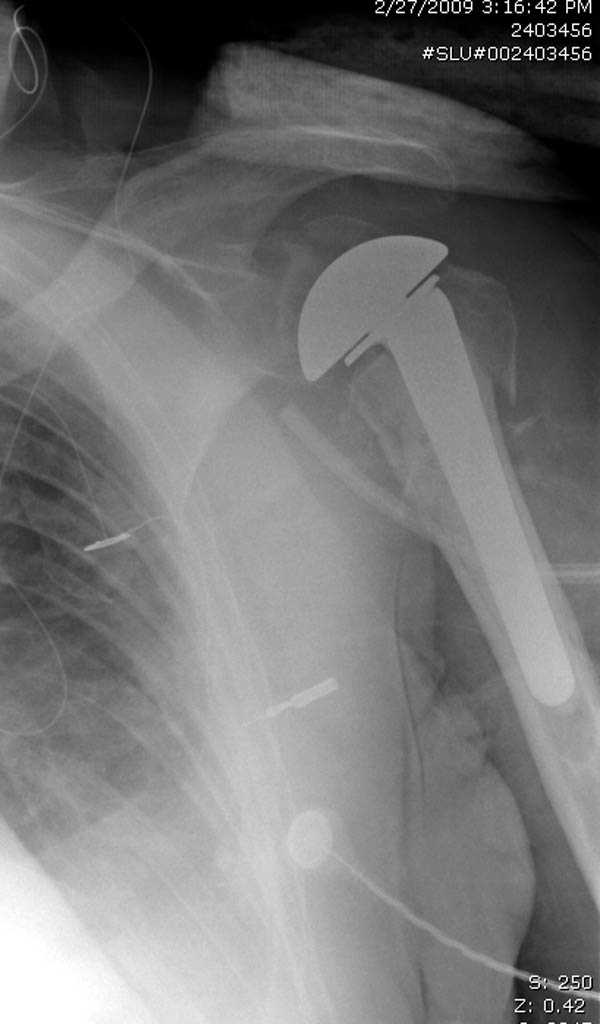

дополнительные снимки по протезированию

Имя     : Shoulder 1.jpg

Тип     : image/jpeg

Размер  : 41951 байтов

Url     : http://weborto.net:8080/pipermail/ortho/attachments/20090420/0ada04e1/attachment-0003.jpg